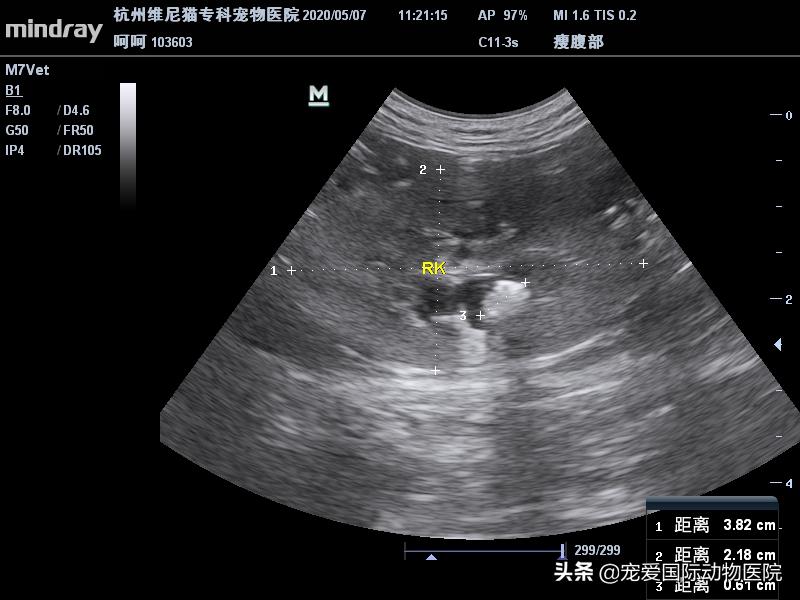

B超检测,见右侧肾盂扩张

内有一直径6MM结石

未见明显扩张输尿管,遂镇静造影

右侧肾结石,右侧输尿管堵塞